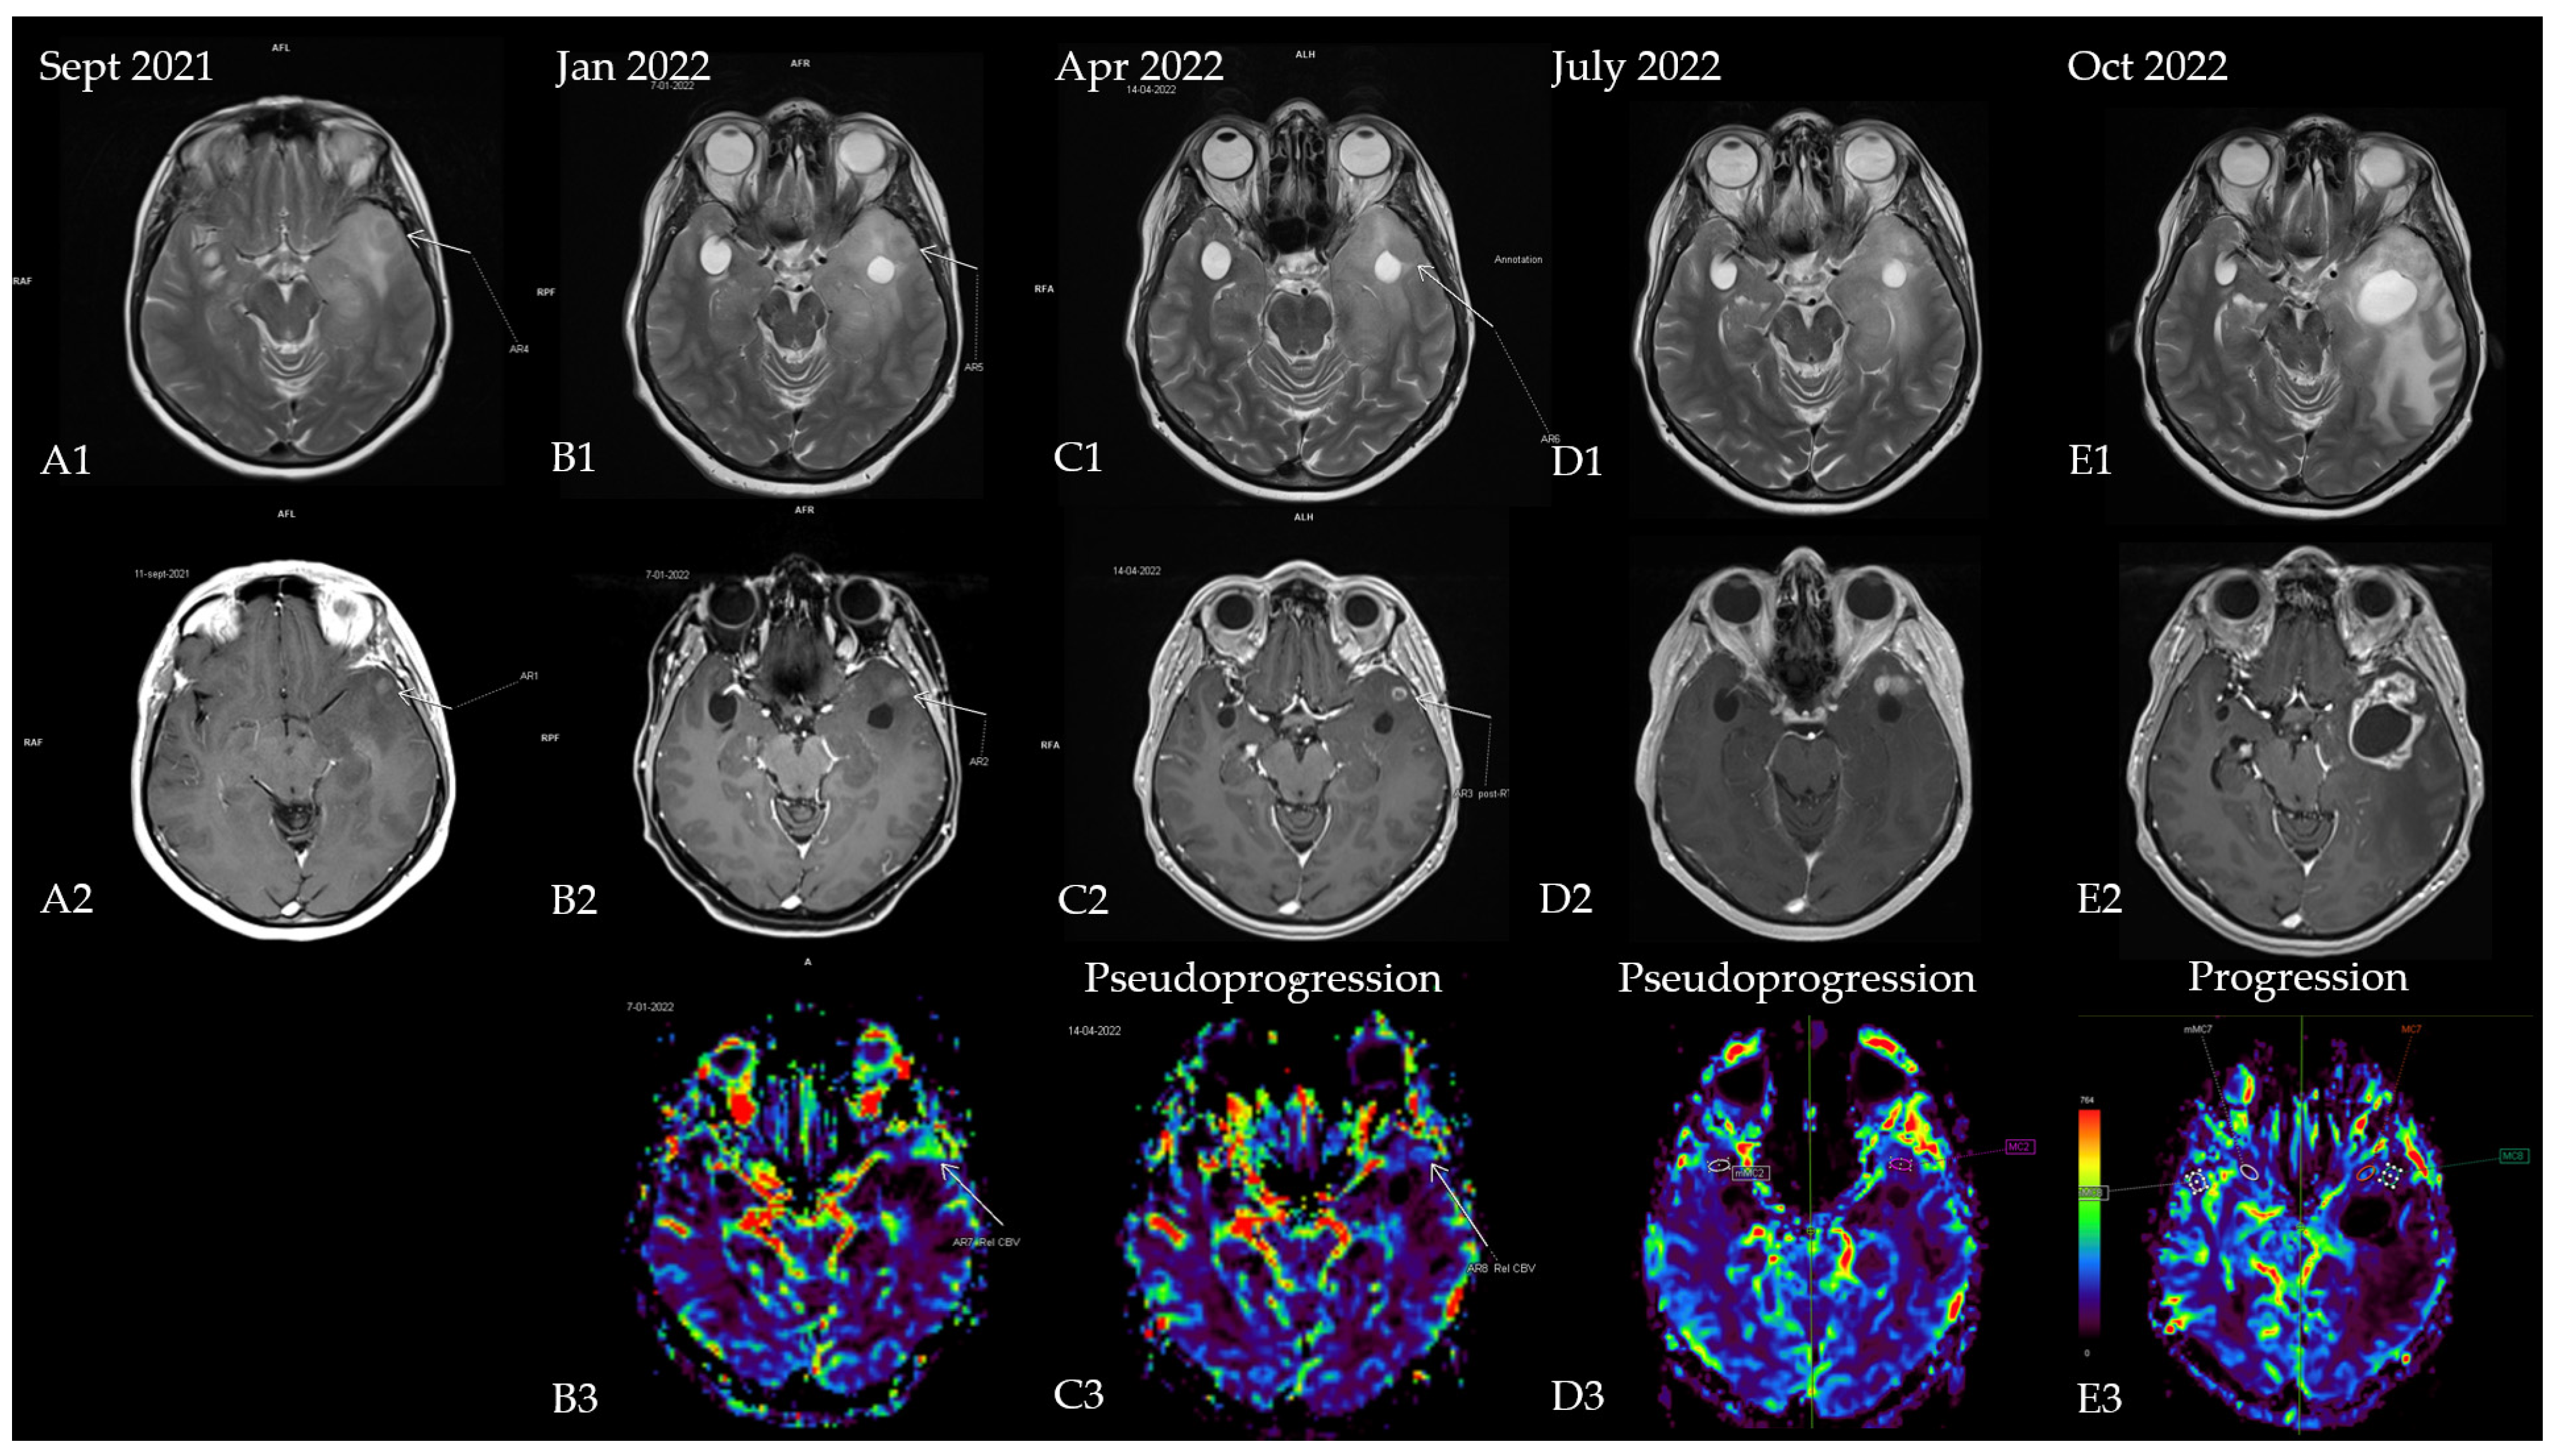

2.1. A Case of Grade 2 Diffuse Astrocytoma Upstaged to Glioblastoma

2.2. A Case of Glioblastoma Downstaged Due to the IDH Status